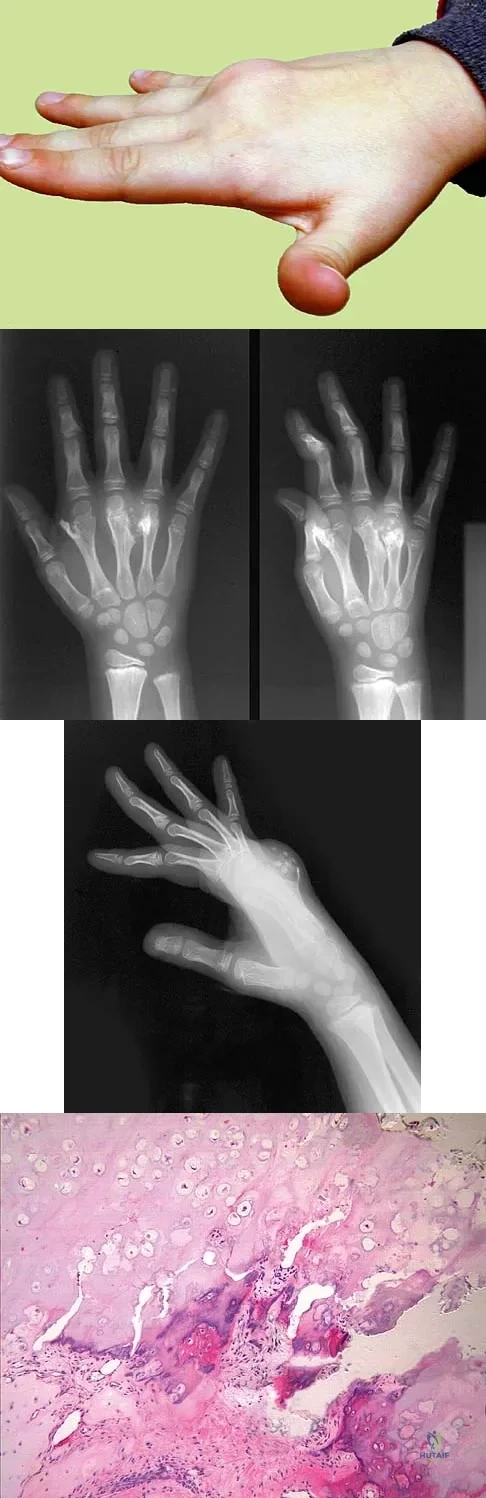

A 9-year-old boy has a painless enlarged mass on the dorsum of his hand. Figures 14a through 14d show the clinical photograph, radiographs, and biopsy specimen. What is the most likely diagnosis?